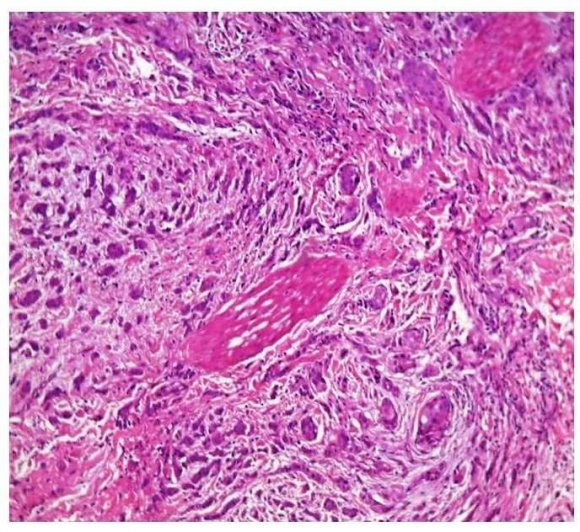

44 cases of female breast cancer were under study. The ages ranged between 33 and 67 years. The age group that had the most number of cases was 41 to 50 years. The commonest histological grade in our study was Grade 2, with 24 cases and 9 cases were grade 3(Fig: 1).

Fig. 1: Invasive ductal carcinoma NOS, H&E 400x 88% of the tumours were of the infiltrating ductal carcinoma, not otherwise specified (NOS). Two cases of micro papillary carcinoma, a case of metaplastic carcinoma and papillary carcinoma were included. Most cases (22) were of sizes between 2cm-5 cm. Lympho vascular invasion was seen in 20 out of 44 cases, with most cases belonging to Grade 2. Perineural invasion (Fig: 2) was seen in only two cases.